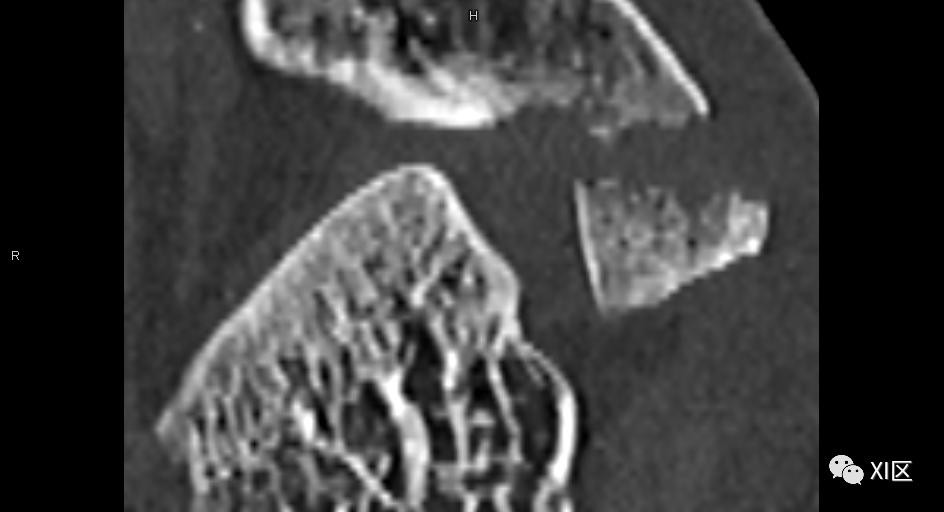

注意骨皮质边缘的锯齿状改变

临床例案例,L2椎体骨折,清楚地显示了与64排/64层和传统模式相比,64排/128层模式空间分辨率的提高。

上图显示了不同模式的临床示例的比较。特别是与传统的CT扫描仪相比,脊柱的轮廓更清晰,可以看到更多的细节。